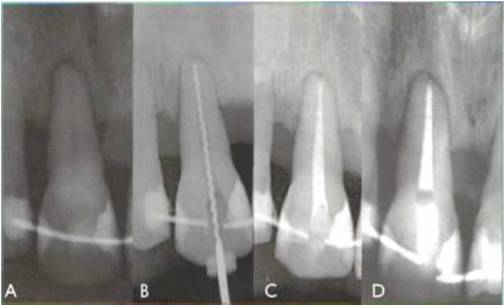

Fig. 10 dintele 1.1 : diagnosticul inainte de tratament: gangrena; A - inainte de tratament; B - evaluarea radiologica a lungimii radiculare; C - metoda de condensare la rece a conului de gutaperca; D - la 6 luni dupa obturatia canalara;